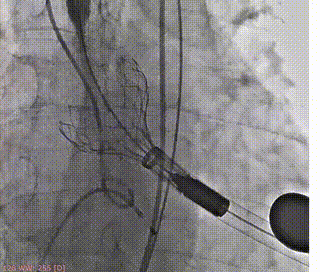

术前造影(左右窦重合体位)

释放支撑臂

支撑臂释放后定位

瓣叶交界贴合释放瓣膜

23mm球囊后扩

最终造影评估